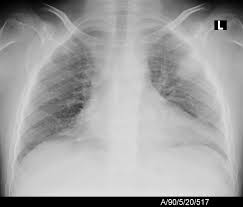

The chest radiograph reveals a left lower lobe opacity with pleural effusion.pneumonia lingula of left upper lobe. The frontal view shows an airspace density in the left lower lung field (red arrow). The chest radiograph reveals a left lower lobe opacity with pleural effusion. Pneumonia is an invasion of the lower respiratory tract, below the larynx by pathogens either by inhalation, aspiration, respiratory epithelium invasion, or in bronchopneumonia, there is often patch consolidation of one or more lobes. This can often be appreciated on a frontal view. Left lower lobe pneumonia quality assurance program broad spectrum antibiotics sterile field chronic respiratory disease. Ap cxr showing left lower lobe pneumonia associated with a small left sided pleural effusion. • both infiltrates are located below the major fissures.

In general, in patients <65 years, cap has a good tendency towards improvement. Pneumonia may manifest as upper abdominal pain when lower lobe infection irritates the diaphragm. The chest radiograph reveals a left lower lobe opacity with pleural effusion. Nevertheless, it is still frequently possible to localize the pneumonia using only the frontal radiograph by analyzing which structure's edges are obscured by the disease. Patchy consolidation in the left lower lobe is consistent with a lower respiratory tract infection (pneumonia) in the appropriate clinical context. Seen only on the pa view. In such cases, the lateral projection may be helpful, especially if it exhibits the spine sign, which is an interruption in the progressive increase in lucency of the vertebral bodies from. Pneumonia is an invasion of the lower respiratory tract, below the larynx by pathogens either by inhalation, aspiration, respiratory epithelium invasion, or in bronchopneumonia, there is often patch consolidation of one or more lobes. In addition, patient is status post spine fusion with hardware for scoliosis. Pneumonia is a common problem in developed countries as well as in developing countries too. Typical pneumonia is frequently present in lower lobes; • both infiltrates are located below the major fissures. For example, pneumonia of left lower lobe is coded to 486.